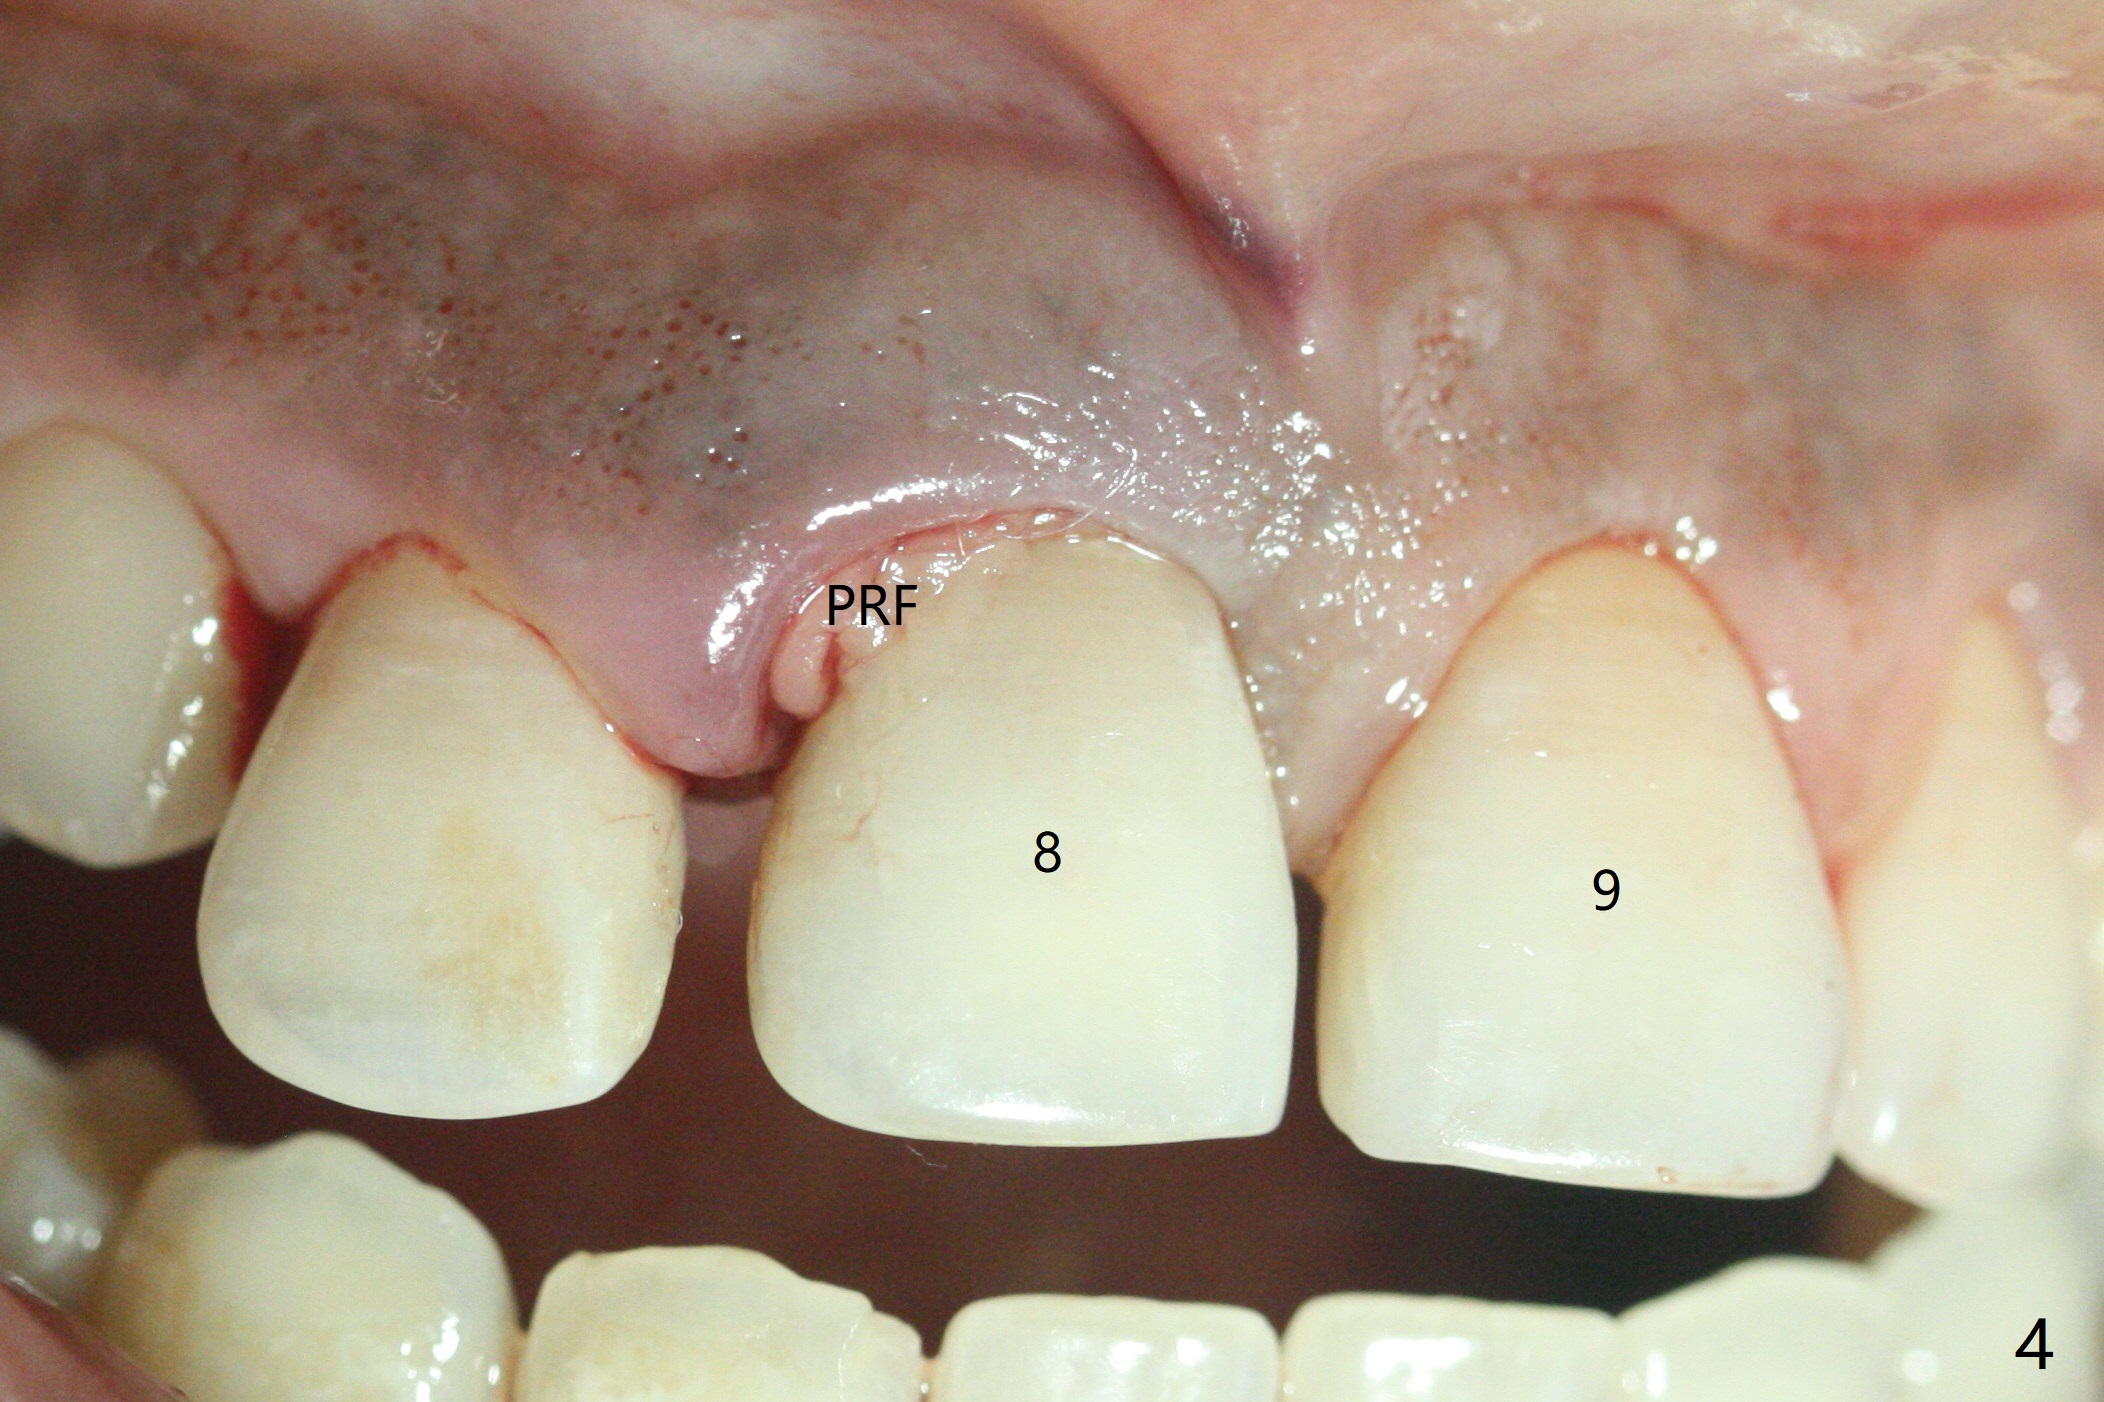

50岁女8号牙远中颊侧冠方移位(图一),牙根暴露(*),前磨牙-前磨牙开合,腭侧牙龈红肿。拔除清创后,使用导板钻洞,徒手植入2.5x13毫米一段式植体,首先将PRF膜插入腭侧,剩余牙槽窝空间植入粘性骨粉(图二:*)。截断拔除牙齿,牙冠掏空,反复调整牙冠长度,使用流动性树脂(flowable composite,图三:*)衬里固定牙冠(C),恰好PRF封闭远中颊侧牙槽窝开口(图四),自然牙冠和一段式植体配合,形成最佳emergency profile,最后牙周敷料进一步封闭牙槽窝(图五),防止骨粉早期脱落,不必担忧敷料不透气。腭侧牙龈红肿(图六)。服用Augmentin两天,患处没有触痛了(图七)。术后九天颊侧牙龈继续延长(图八).